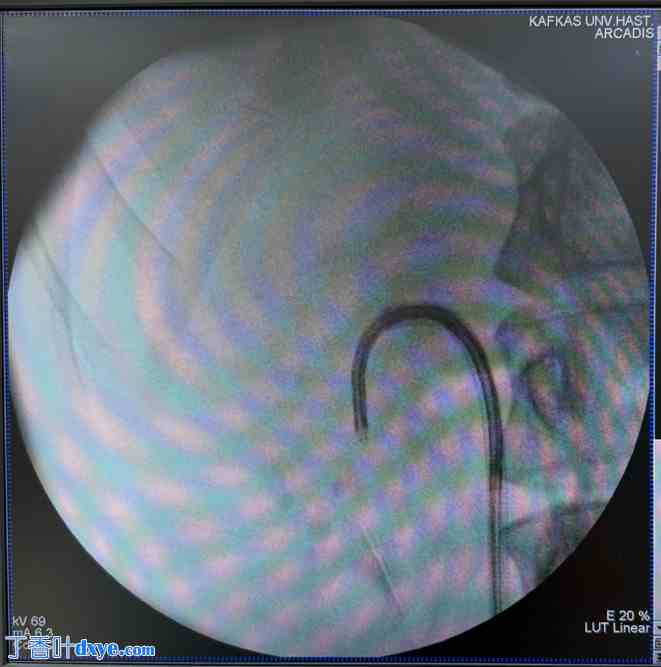

在此阶段之后,对于接受 FANS 手术的患者,将一个具有可弯曲尖端和抽吸功能的通路鞘(12/14 Fr),通过导丝放入相关输尿管直至肾盂。一次性使用柔性内窥镜(7.5 Fr)穿过通路鞘,详细检查肾脏集合系统。完成此操作后,在柔性 URS 的引导下,将放置的通路鞘的尖端推入下肾盏位置(图 1),并使用钬光纤用 273 µm 光纤将结石粉碎。在该组中,结石被碎裂成足够大小(< 3 mm),以便在主动抽吸的帮助下有效取出。

图 1.

在柔性输尿管肾镜引导下,将柔性可导航的导尿管鞘推入肾盏下部